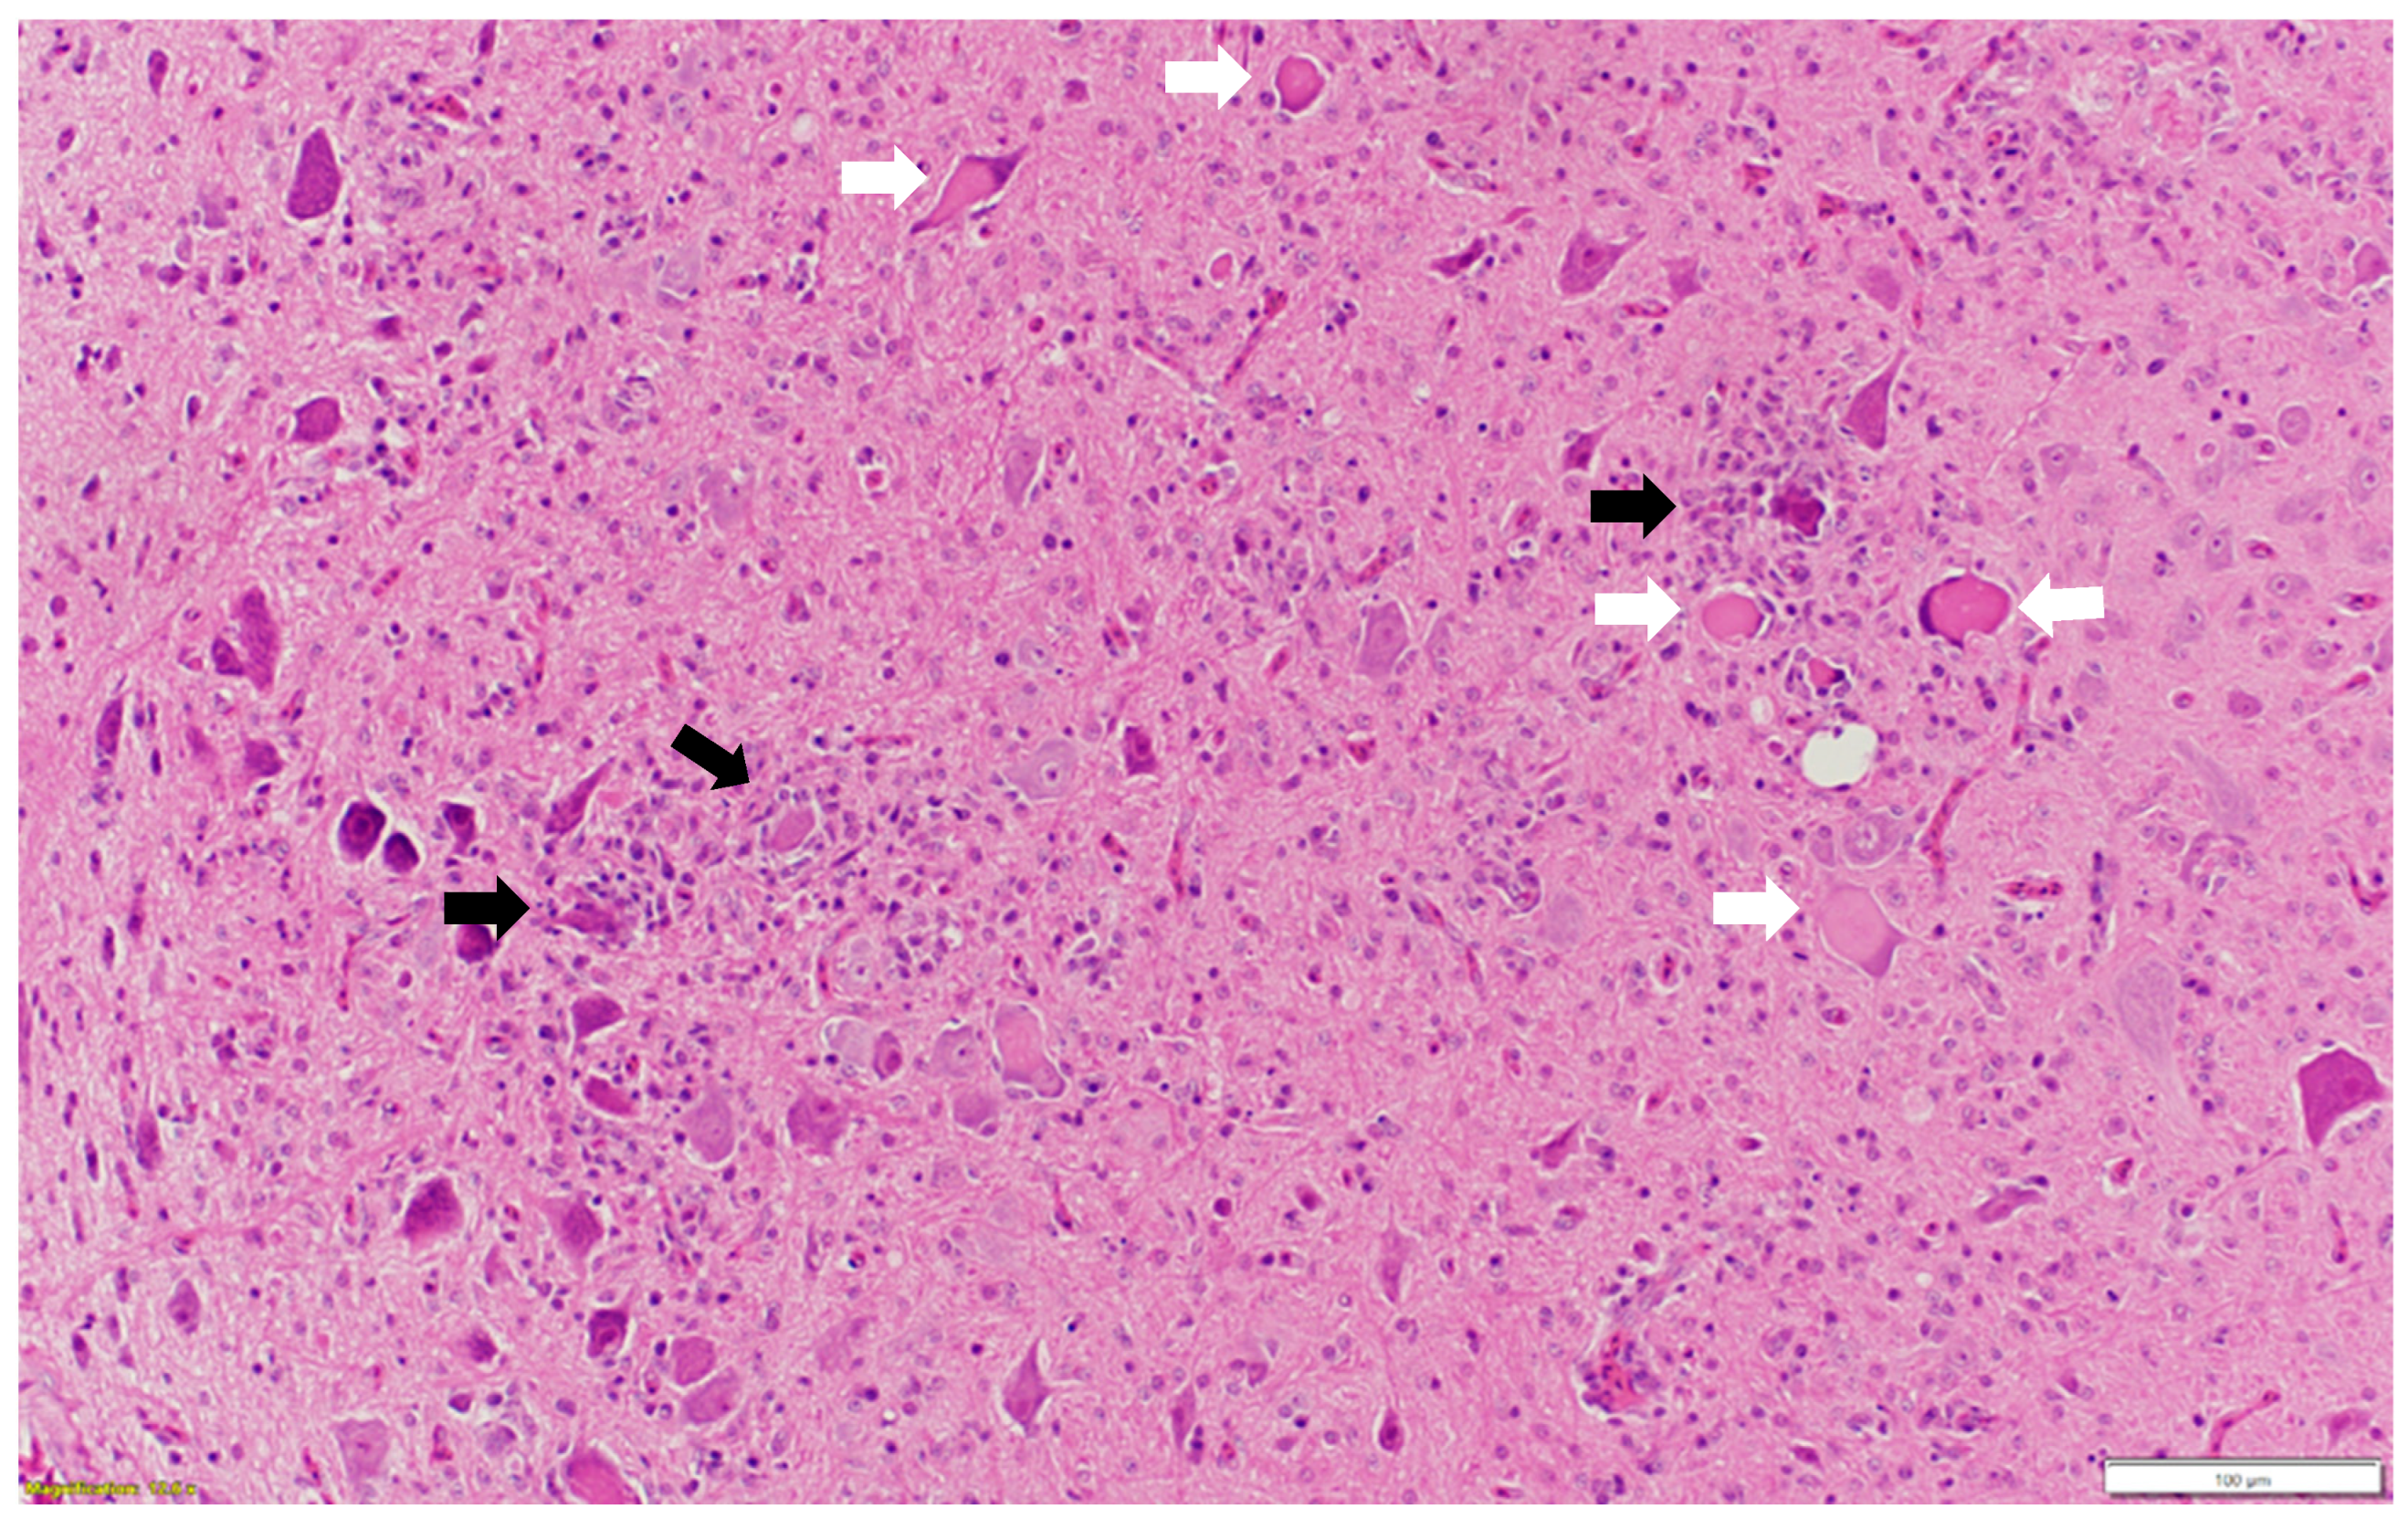

Microscopic examination of different brain, spinal cord, peripheral nerves, and ganglions sections revealed multifocal areas of lymphoplasmacytic and histiocytic infiltrates, indicating encephalitis (Figure 1) in the cerebral white matter, thalamus, hippocampus, and medulla oblongata close the ventricular space. The inflammatory cells around the vessels (perivascular cuffing) as well as around the neurons (satellitosis and neuronophagia) resulted in several neuronal degeneration and central chromatolysis (Figure 2). The gray matter in the spinal cord had multifocal lymphoplasmacytic infiltrates, indicating myelitis (Figure 3). In addition, there was mild to moderate multifocal ganglioneuritis in the pelvis ganglions (Figure 4).

Figure 2.

Multiple neurons with central chromatolysis (white arrow: pathognomonic for AEV) and inflammatory cells around degenerated neurons (black arrow: satellitosis and neuronophagia). Paraffin-embedded tissue was stained with hematoxylin and eosin.